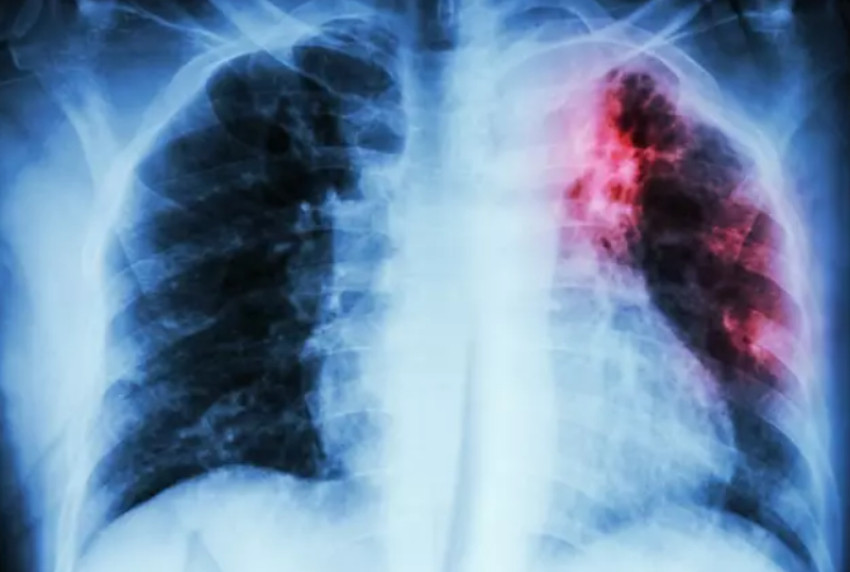

Prevención y detección para el cáncer de pulmón. Esta es la razón que ha llevado a poner en marcha una prueba piloto que hará cribajes entre fumadores y exfumadores mediante un TAC. En la iniciativa participarán una cuarentena de hospitales públicos de España, de los cuales 9 son de Catalunya.

Según este médico, más de 80% de los cánceres se detectan "en fase localmente avanzada o avanzada", de modo que las esperanzas de supervivencia se reducen drásticamente.